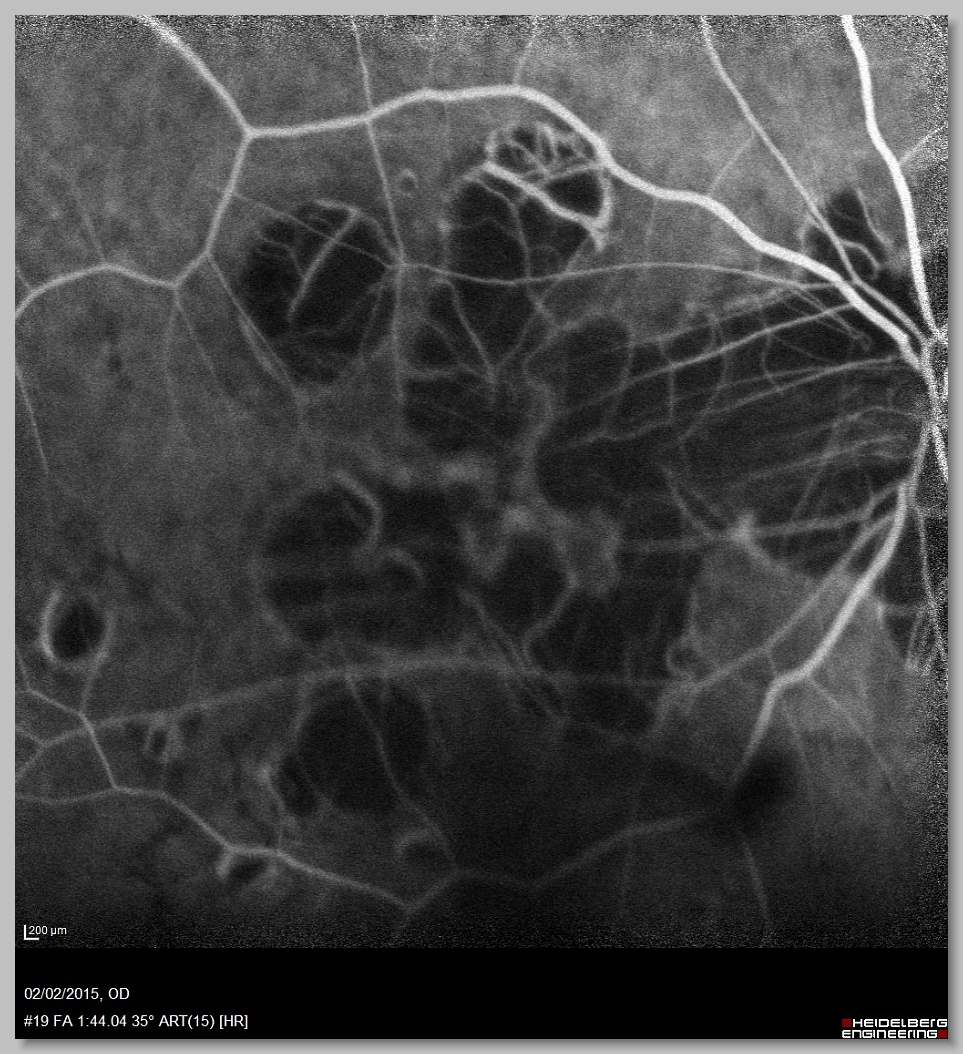

OCT 004 OCT 005 FA 000 FA 001

FA 002 FA 003 FA 004 FA 005

FA 006 FA 007 FA 008 FA 009

FA 010 FA 011 FA 012 FA 013

FA 014